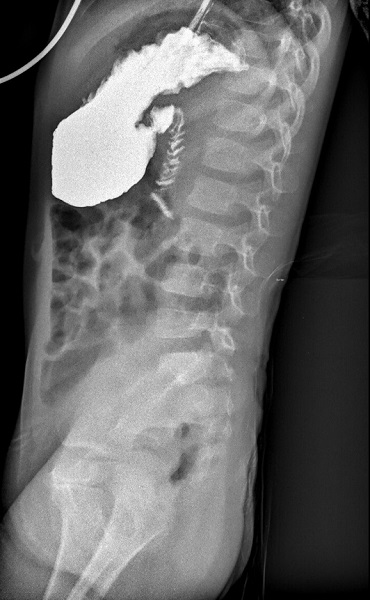

Debido a la persistencia de la distensión abdominal, se realiza una ecografía abdominal, que resulta normal y una radiografía de abdomen simple, donde se aprecia distensión de asas abdominales hasta íleon terminal, que inicialmente se asocia a posible gastroparesia posinfecciosa. Posteriormente, se amplía el estudio con un tránsito gastro-duodenal, objetivándose un “stop” al paso de contraste baritado en segunda/tercera porción duodenal-ángulo de Treitz (Figura 1). Ante la sospecha de obstrucción intestinal por una membrana duodenal, se indica una gastroduodenoscopia, que resulta normal.

| Figura 1. Tránsito digestivo superior. Se visualiza un stop a la progresión del contraste a partir del ángulo de Treitz. Dilatación del territorio proximal al stop |